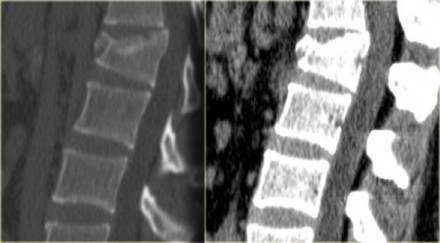

lwk en ct sag

On the left images of a 31 year old male.

He was working on a roof, fell approximately 5 meters landing on his feet.

He complained of pain in left lower extremity and lower back.

First study the images, then continue reading.

On the x-ray there is a hyperflexion injury of L1 with involvement of the anterior column and possible involvement of the middle column.

The sagittal reconstructions of the CT demonstrate that the posterior part of the vertebral body is of normal height, but there is some involvement of the posterior part of the vertebral body.

There is debate on how to treat these patients and if there is any role of MRI in these cases.

If you are aggressive you could call this a two column injury, which would require stabilizing surgery.

If you are conservative you could call this an injury with only minor involvement of the middle column.